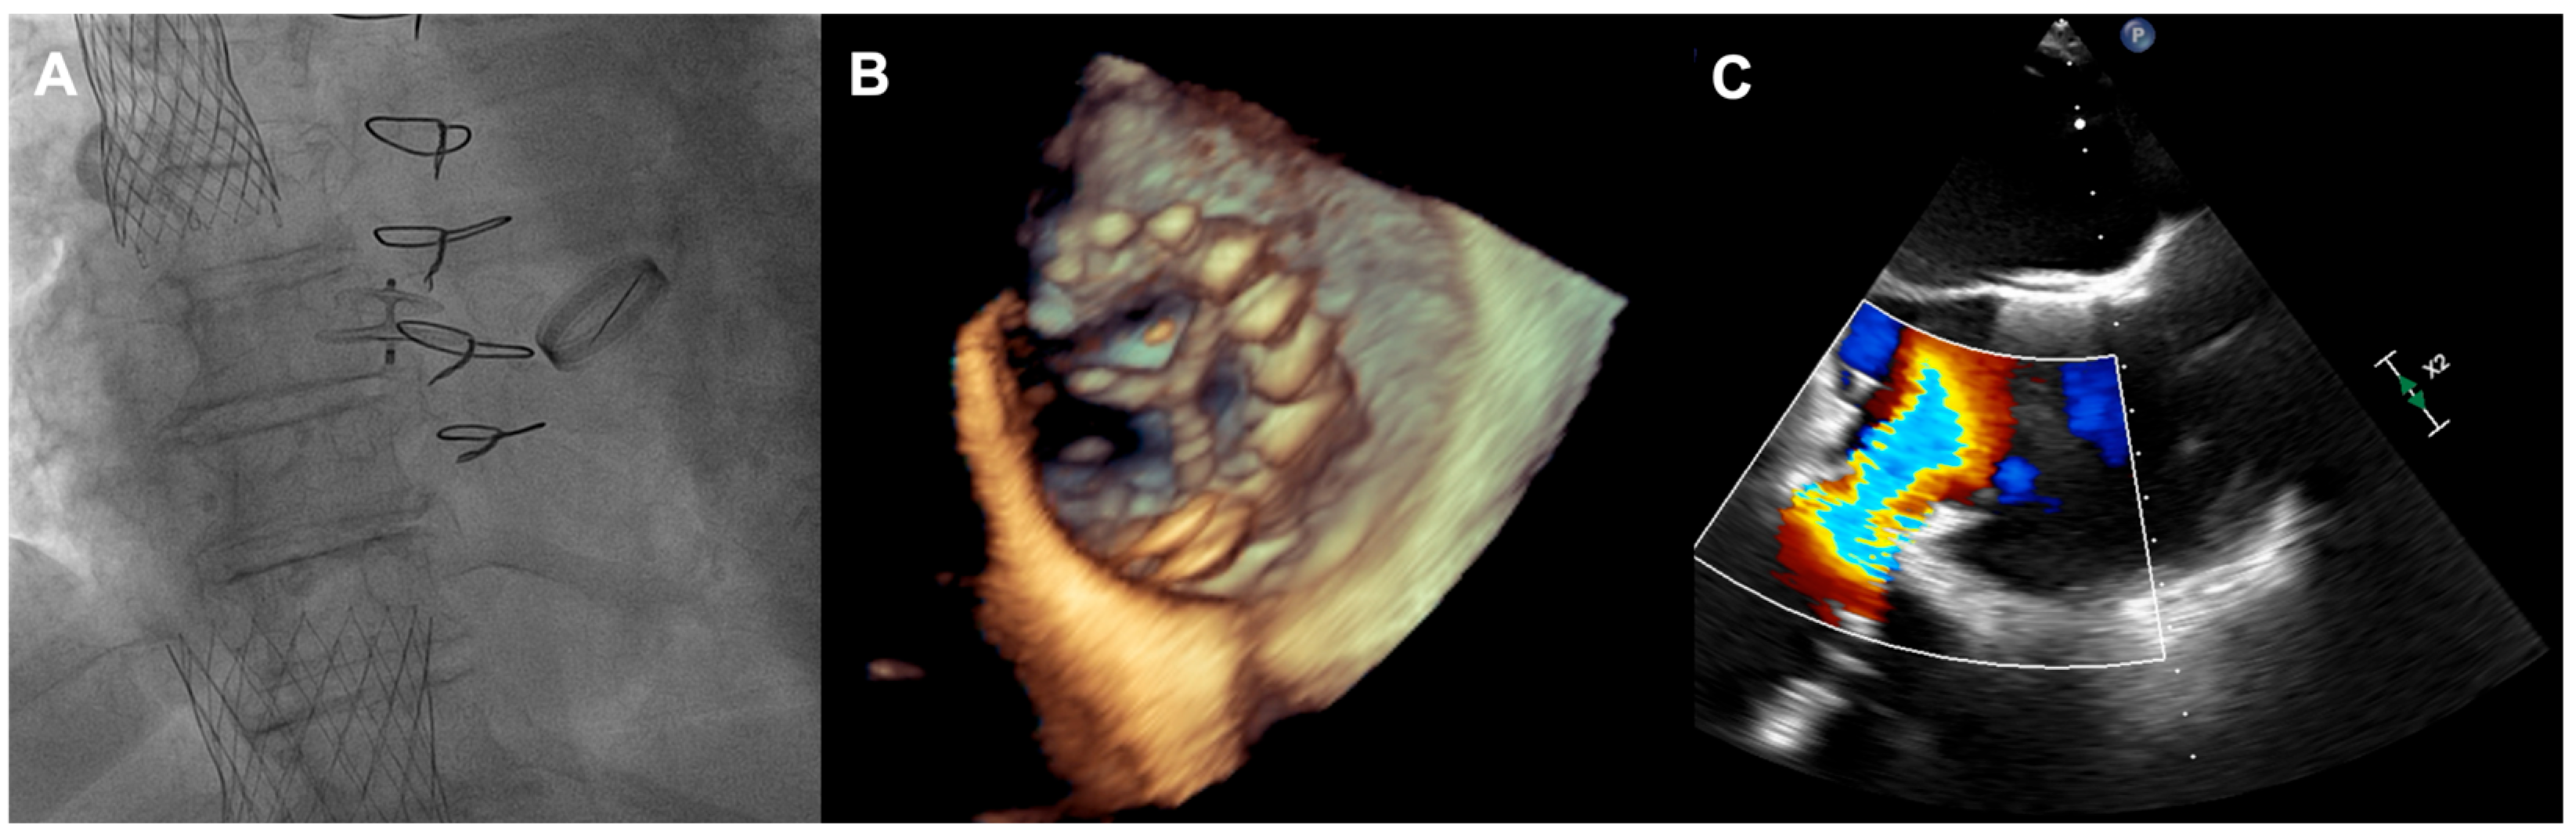

A 73-year-old woman with a history of two surgical interventions—an aortic valve replacement 25 years before and a thoracic aortic aneurysm repair 12 years before—was admitted to the hospital because of persistent heart failure symptoms in functional class NYHA III, accompanied by peripheral edema and ascites. The transthoracic echocardiography showed preserved function of the mechanical aortic prosthesis and torrential TR with tricuspid anulus enlargement. A further transesophageal examination revealed a large, mainly central coaptation deficit between the tricuspid leaflets, located mainly in the central region of the valve (Figure 3). Furthermore, a patent foramen ovale (PFO) with spontaneous right-to-left shunt was also diagnosed. Due to the valve anatomy, the patient was not deemed eligible for the transcatheter edge-to-edge repair. Because of the symptoms’ persistence, a two-step percutaneous procedure was planned. First, the PFO was closed with the 25 mm Amplazer occluder. Two weeks later, the CAVI procedure with the implantation of TricValve system valves (SVC 29 mm; IVC 45 mm) was carried out without complications. (Figure 4) We believed that the PFO closure was necessary before the CAVI procedure because the implantation of venae cavae valves in a patient with a patent PFO would have caused an exacerbation of the right-to-left shunt and possible patient desaturation. In observation, six and twelve months after the procedure, the patient remained on stable doses of oral diuretics and was considered to be in NYHA functional class II, without worsening heart failure or requiring hospitalization.

Figure 3. (A,B) Torrential tricuspid regurgitation in the RV inflow—outflow tract X-plane view; (C) large central coaptation deficit in 3D view. RV—right ventricle.

Figure 4. (A) Final angiographic result of TricValve implantation; (B) 3D view of IVC valve protruding to RA; (C) inflow from IVC through the implanted valve. IVC—inferior vena cava; RA—right atrium.